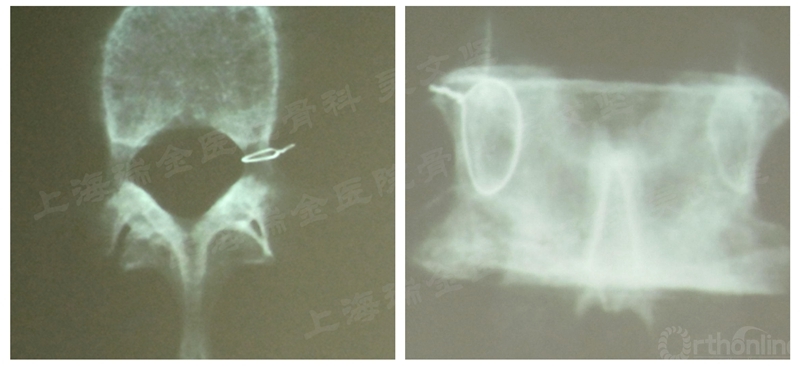

必须指出的是,椎弓根并不是一个规则的圆柱体,而是两端略宽中间略窄的“小蛮腰”形状,而正位透视的椎弓根影实际上是椎弓根最狭窄的腰部的投影(图3),因此进针点往往不一定位于椎弓根影边缘而可能略偏外侧,而透视下Jamshidi如果到达椎弓根内侧缘,在椎弓根根部可能还有少量骨质,只要手感良好,应该也是安全的。

图3 正位透视的椎弓根影实际上是椎弓根最狭窄的腰部的投影